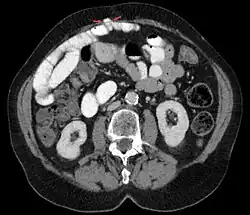

Grynfeltt-Hernie links in der Computertomographie.

Petit-Hernie links in der Computertomographie.

Bei lumbalen, also im Lendenbereich auftretenden Hernien erfolgt der Durchtritt von Fett oder anderen abdominellen Strukturen nach hinten außen entweder oben unterhalb der 12. Rippe durch das Trigonum lumbale superius (Grynfeltt-Hernie) oder unten oberhalb des Beckenkamms durch das Trigonum lumbale inferius (Petit-Hernie).